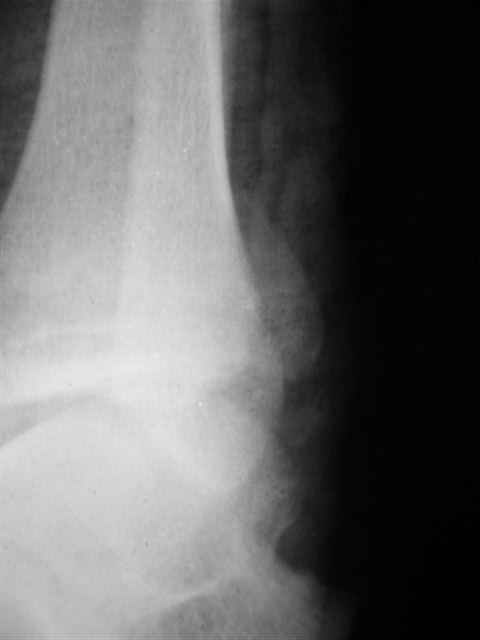

открытый перелом мыщелков бедра, латерального плато большеберцовой кости. надколенника

Уважаемые коллеги,молодой человек 18 лет переведен к нам через 12 часов с момента автоаварии.

Повреждений внутренних органов нет, пульс на тыльной артерии стопы определяется. Общее состояние стабильное, учитывая интоксикацию больного сохранность чувствительности определить проблематично. Хотелось бы знать ваше мнение по тактике и лечению, а именно, насколько целесообразно в данном случае наложение spanning ex fix после обработки и фиксации переломов. При обработке выявлены дефекты передне - срединного отдела суставной поверхности большеберцовой кости и надколенника, которые, учитывая обширность и тяжесть травмы мягких тканей решил отложить до *лучших* времен. На промывание раны ушло 24 литра стерильного раствора, фиксация переломов бедра и большеберцовой костей тягловыми винтами, надколенника по Веберу.Имелась травма голеностопа Вебер тип С( закрытый) (фиксация винтами и спицами) Заранее благодарен,Евгений И Чекашкин